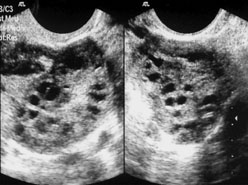

سندرم تخمدان پلی کیستیک (PCOS) شایعترین اختلال غدد درونریز در زنان و یکی از دلایل عمده ناباروری به شمار میرود.

ابتلا به این سندرم معمولا با اختلالات متابولیکی از جمله افزایش قند و چربیهای خون، پرفشاری خون و همچنین افزایش آندروژنها (هورمونهای مردانه) بهویژه تستوسترون، رشد موهای زاید (هیرسوتیسم) و چاقی همراه است.